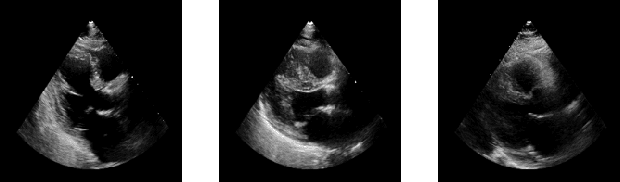

Abstract:Capsule Neural Networks (CapsNets) is a novel architecture that utilizes vector-wise representations formed by multiple neurons. Specifically, the Dynamic Routing CapsNets (DR-CapsNets) employ an affine matrix and dynamic routing mechanism to train capsules and acquire translation-equivariance properties, enhancing its robustness compared to traditional Convolutional Neural Networks (CNNs). Echocardiograms, which capture moving images of the heart, present unique challenges for traditional image classification methods. In this paper, we explore the potential of DR-CapsNets and propose CardioCaps, a novel attention-based DR-CapsNet architecture for class-imbalanced echocardiogram classification. CardioCaps comprises two key components: a weighted margin loss incorporating a regression auxiliary loss and an attention mechanism. First, the weighted margin loss prioritizes positive cases, supplemented by an auxiliary loss function based on the Ejection Fraction (EF) regression task, a crucial measure of cardiac function. This approach enhances the model's resilience in the face of class imbalance. Second, recognizing the quadratic complexity of dynamic routing leading to training inefficiencies, we adopt the attention mechanism as a more computationally efficient alternative. Our results demonstrate that CardioCaps surpasses traditional machine learning baseline methods, including Logistic Regression, Random Forest, and XGBoost with sampling methods and a class weight matrix. Furthermore, CardioCaps outperforms other deep learning baseline methods such as CNNs, ResNets, U-Nets, and ViTs, as well as advanced CapsNets methods such as EM-CapsNets and Efficient-CapsNets. Notably, our model demonstrates robustness to class imbalance, achieving high precision even in datasets with a substantial proportion of negative cases.